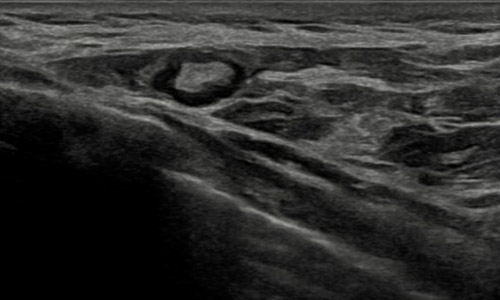

- Valoración de ganglios axilares en el contexto de un carcinoma mamario de reciente diagnóstico.

Ganglio axilar normal en ecografía